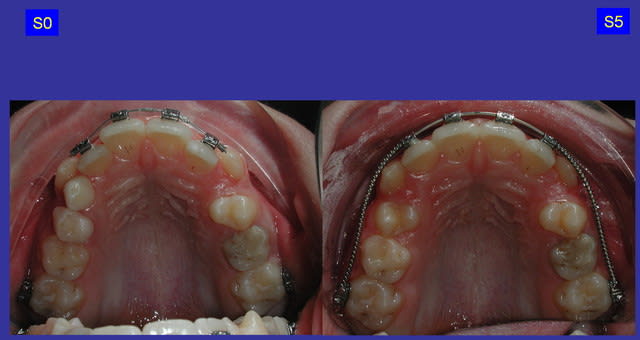

> suite : occlusale

Suite...